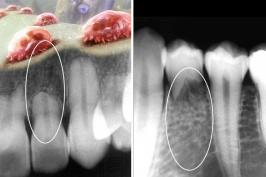

A raiz sumiu: dentes são reabsorvidos